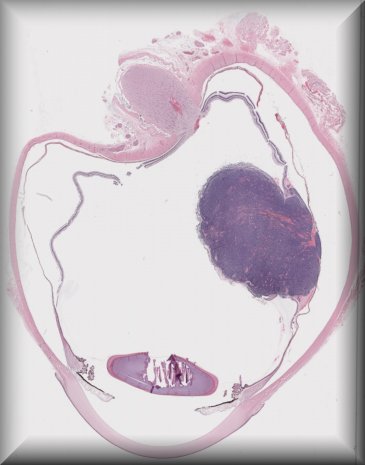

Alexandre Moulin (Laussane): Pigmented ciliary body mass in a 35 yo male. |